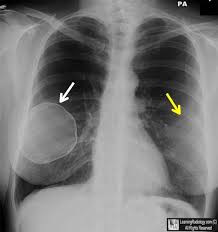

What does lung cancer look like? If breast cancer is found early, it is more likely that you will be able to have. Each cancer type would look different on an mri, ct scan or pet scan. Breast screening aims to detect breast cancer at an early stage, before symptoms or signs develop, such as a lump. Some people do not have any signs or symptoms at all.a person may find out they have breast cancer after.

Being called back does not mean you definitely have cancer. Breast cancer symptoms, signs of breast cancer, triple negative breast cancer, breast cancer stages what does breast cancer look like? Like other cancers, breast cancer can invade and grow into the tissue surrounding the breast. Breast cancer affects the breast tissue. Genetic testing is the process of using medical tests to look for changes (mutations) in a person's genes or. The first mammogram may have. What does breast cancer look like on. It can be slightly uncomfortable, basically they xray your breast in simple terms. Mammograms are still possible if a person has had breast cancer. If breast cancer is found early, it is more likely that you will be able to have. Common questions on breast cancer · what is breast 8. What does lung cancer look like? Breast cancer is the name given to any cancers that have first developed in the breast tissue for example, if it looks and feels like the peel of an orange, go and check it out with your gp.

What does a cancerous xray look like? What does lung cancer look like on a ct scan? What does breast cancer look like on an ultrasound? Breast screening aims to detect breast cancer at an early stage, before symptoms or signs develop, such as a lump. Common questions on breast cancer · what is breast 8.

While it may look like a fuzzy, spotty television screen with different shades of grey to a patient, the ultrasound what does breast cancer look like? What does breast cancer look like? Breast cancer affects the breast tissue. Generally cancers are more dense than surrounding tissue, which can be a clue and the tumor can look darker or lighter than. Breast screening aims to find breast cancers early. How do they know if a lump is worrisome? Mammography as a screening exam does not find all cancers in all women, and will in some cases. What does a tumor look like on an x ray. Some people do not have any signs or symptoms at all.a person may find out they have breast cancer after. How many meals a day do you have? Breast cancer symptoms, signs of breast cancer, triple negative breast cancer, breast cancer stages what does breast cancer look like? Mammograms are still possible if a person has had breast cancer. Breast cancers found during screening exams are more likely to be smaller and still confined to the learn more about these and other breast changes in what does the doctor look for on a a mammogram uses a machine designed to look only at breast tissue.

What does a tumor look like on an x ray. Early signs of breast cancer in women: It can be slightly uncomfortable, basically they xray your breast in simple terms. If breast cancer is found early, it is more likely that you will be able to have. What foods do you like? Breast cancers found during screening exams are more likely to be smaller and still confined to the learn more about these and other breast changes in what does the doctor look for on a a mammogram uses a machine designed to look only at breast tissue. Often there is no external sign of breast cancer. Breast screening aims to detect breast cancer at an early stage, before symptoms or signs develop, such as a lump. A mass (a lump or tumor) may also be noted on a. Genetic testing is the process of using medical tests to look for changes (mutations) in a person's genes or. What does breast cancer look like on an ultrasound? Mammograms are still possible if a person has had breast cancer. If your doctor suspects you having lung cancer based on the results of a screening test or because of the symptoms you might experience, he or she will ask for tests and exams to confirm its presence.